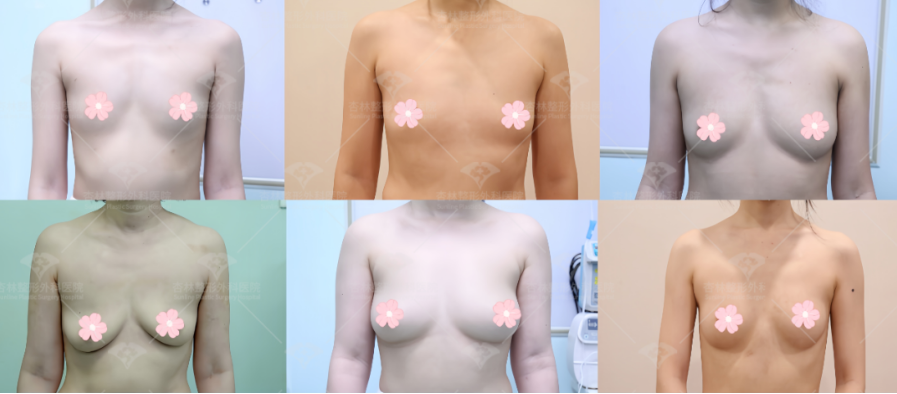

关于乳房松弛下垂,轻度的松弛下垂可以通过做假体丰胸做矫正,通过假体隆胸可以增加乳房的大小,并使乳头上提,得到令人满意的乳房外形。

但针对中重度下垂乳房(伴有重度乳房肥大时),就要根据乳房下垂程度、形态来选择适合的下垂矫正手术,包括乳房悬吊及乳房缩小。

乳房悬吊术是将下垂的乳头及乳房组织进行提升并固定到正常的位置上,一些松弛下垂严重的还要切除多余的乳房腺体和皮肤,切除过大的乳晕,将乳头乳晕“旋转”移动到合适的位置,将乳房腺体重塑成半球形,并固定。双环切口是沿乳晕边缘切开,去除周围部分松弛皮肤后再收紧,恢复后疤痕较为隐蔽。

中、重度的下垂通过单纯隆胸达不到理想效果,需要通过乳房上提术来矫正。一部分患者胸部下垂且偏大,该手术可同时改善,切除缝合后可达到上提乳房的效果。相比前一种垂直短切口,倒T切口乳房上提术多了一条横向痕迹线,但刚好位于乳房下轮廓线上,恢复后不太明显。如果大家还有关于“胸整形”的疑问,可在后台私信我们的客服小姐姐哦~